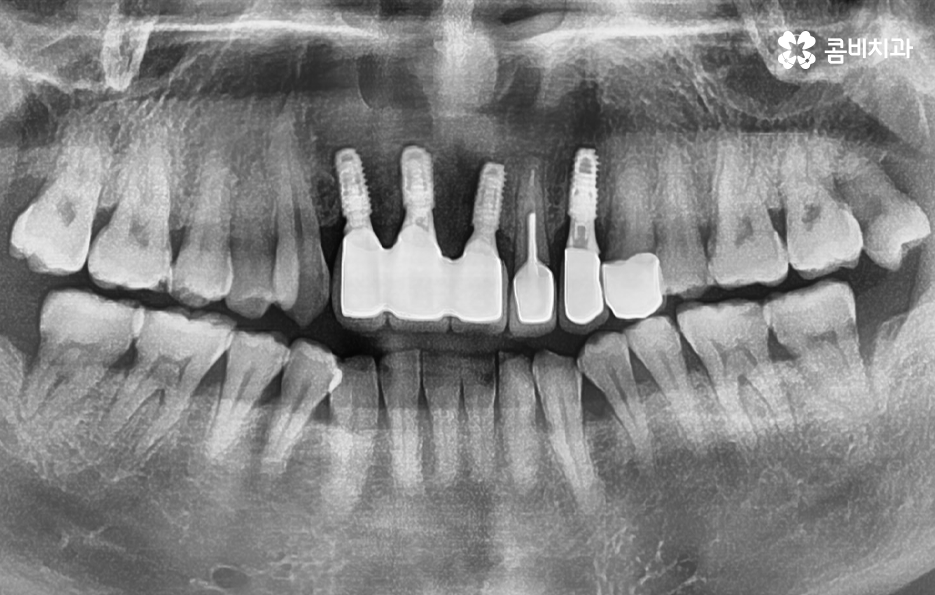

이렇게 앞니가 상실되면 심미적, 기능적 불편이 크기 때문에 많은 분들이 앞이빨 임플란트 과정을 거치게 되는데 앞니 임플란트는 어금니와는 다른 부분에서 좀더 정교한 치료가 필요하며 앞니 부위는 뼈가 얇고 심미성이 중요한 부위라는 점에서 잇몸 라인, 앞니의 각도, 심미성, 주변 치아와의 조화까지 모두 맞아야 자연스럽게 보이므로 정교한 치료의 중요성이 더 높은 부위라고 할 수 있어요

그리고 앞니는 씹는 힘이 약해 보이지만 가로 방향 힘이 많이 가해져서 임플란트에 부담을 주기 쉽고 앞니 상실의 원인이 치주염이라면 뼈가 많이 녹아 있는 경우가 많아 뼈 이식이 필수적인 상황이 자주 생기므로 앞이빨 임플란트 과정에서 주의해야 할 점들에 대해 잘 알고 접근하는 것이 중요한 거예요

또한 앞니는 잇몸의 모양이 심미성에 큰 영향을 주는데, 잇몸이 얇으면 임플란트가 비쳐 보이거나 잇몸 라인이 붕괴될 위험이 있어서 이런 경우에는 잇몸 두께를 보강하는 잇몸 이식술이 필요할 수 있으며 앞이빨 임플란트 과정 뿐 아니라 치료 후에도 잇몸 관리는 앞니 임플란트의 수명, 심미적인 유지에 있어서 중요한 요소라고 볼 수 있었어요

앞니는 사람들에 따라서 상실 원인이 다르고 현재의 잇몸 및 전신건강 상태가 다르며 특히 중년이후에는 기존의 보철물이 노후되거나 치주염으로 인해 치아를 상실하는 경우도 많기 때문에 앞이빨 임플란트 과정이라서 해서 단지 빠르게 치료하는 것만이 중요한 것이 아니라 장기적인 안정성 등을 충분히 고려한 치료 계획이 중요하므로 경험 많은 치과의사와 충분히 상의하고 정밀검진 결과를 토대로 나에게 맞는 치료 계획 그리고 사후관리까지 고려한 장기적인 유지까지 고려하여 판단하시길 바라고 있어요